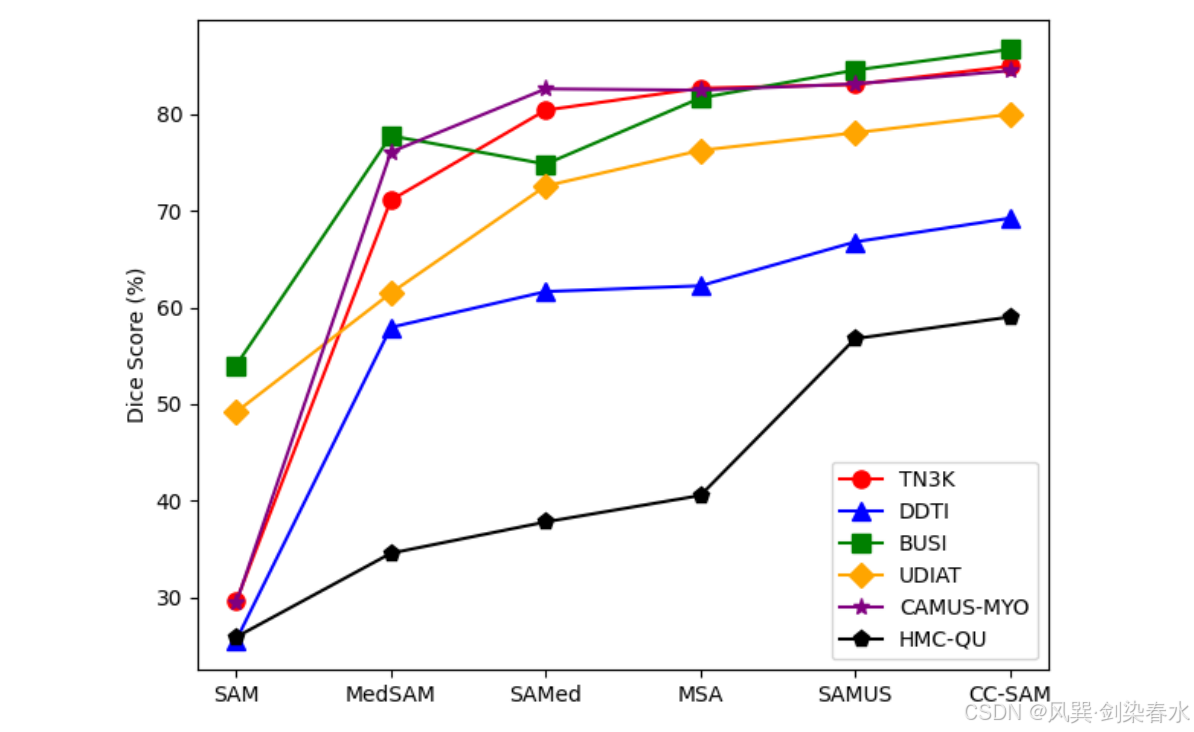

Figure 1 | 使用SAM进行医学图像分割的方法比较:

Figure 7 | CC-SAM 和其他基础模型的分割泛化能力比较: